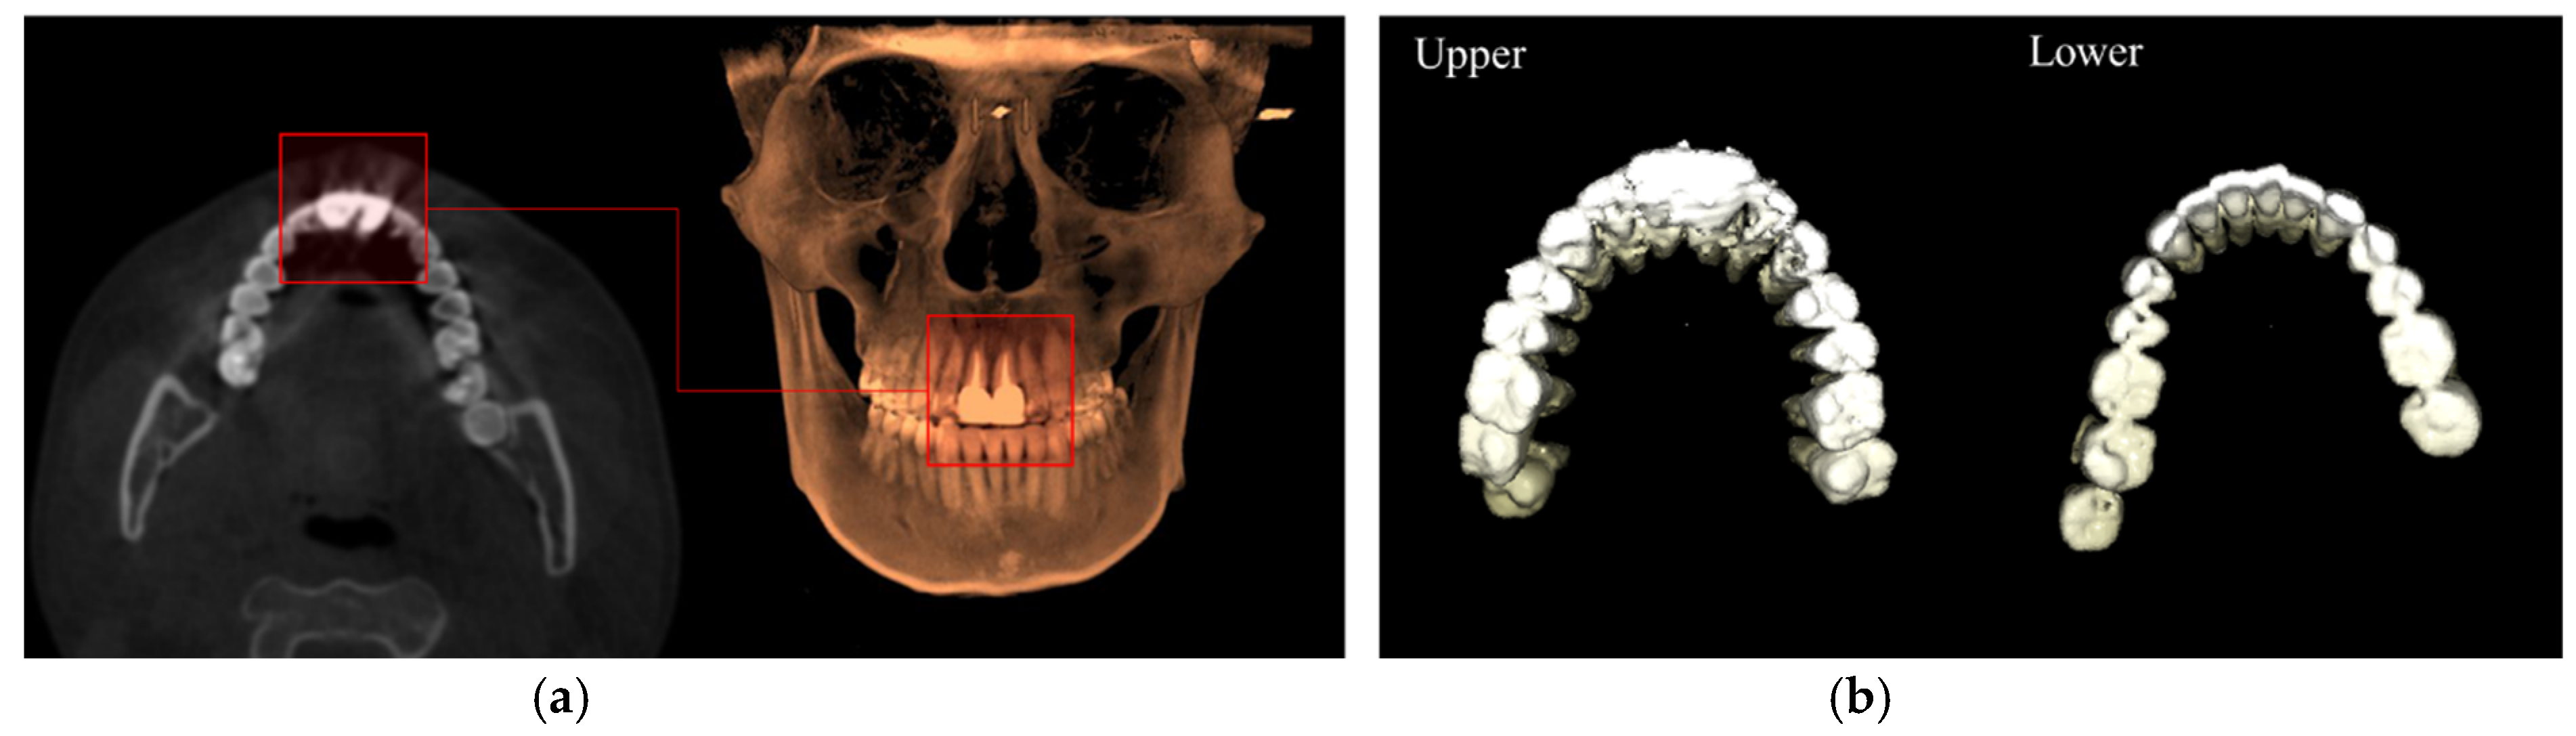

3.1. 3D Upper and Lower Teeth Segmentation from CBCT Data

3.2. Teeth Segmentation from the Scan Images of Plaster Dental Models